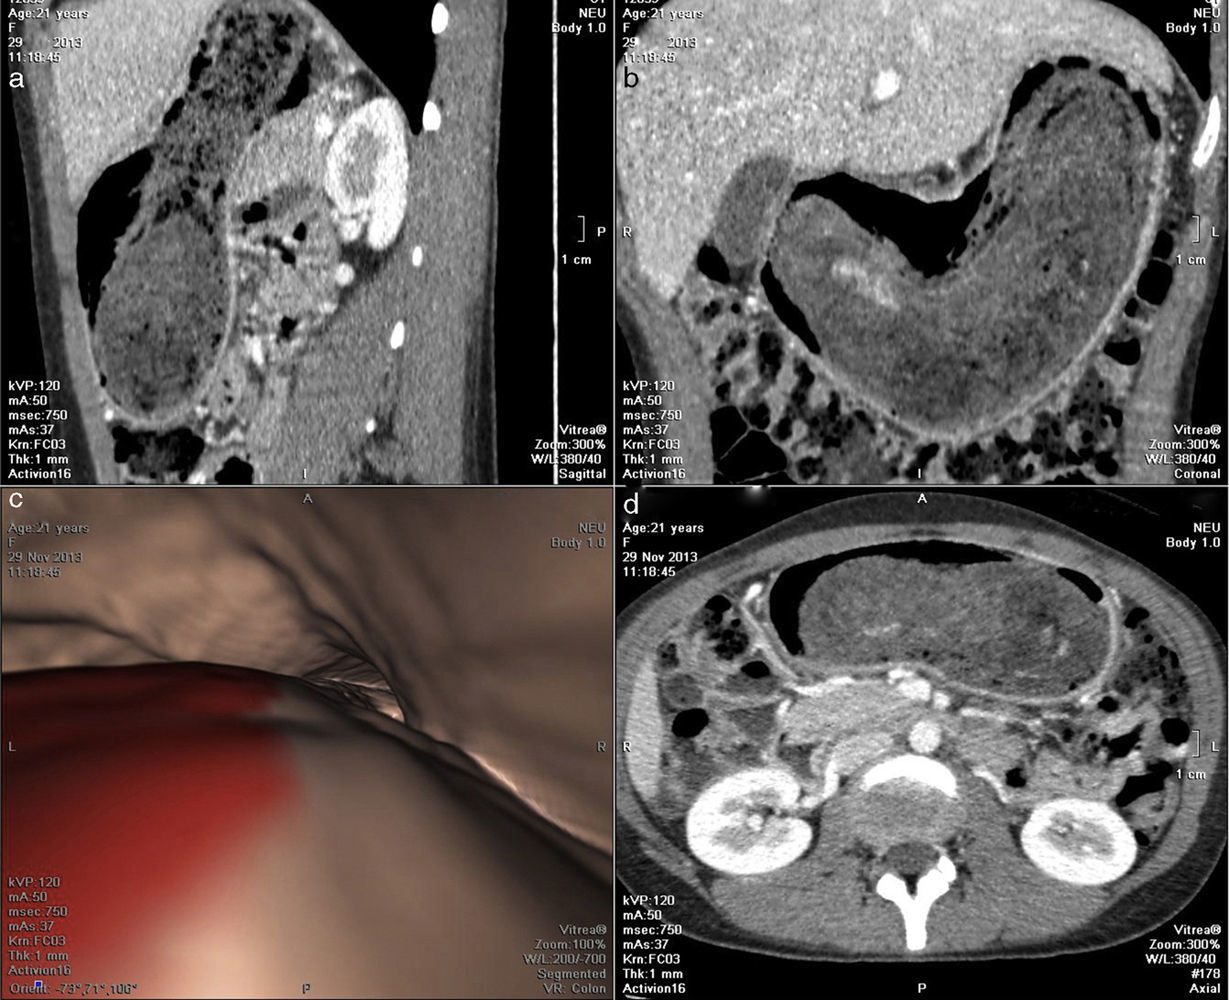

Las radiografías abdominales manifestaron una masa radiopaca ocupando y moldeando la cámara gástrica (fig. 1) y la ecografía de abdomen evidenció una masa gástrica intraluminal con borde hiperecogénico y sombra acústica posterior, sugestiva de bezoar (fig. 2). Por su parte, la neumo-TC mostró una masa con densidad de partes blandas heterogénea y aire en su interior, que moldeaba la cámara gástrica y era compatible con tricobezoar (figs. 3 y 4). Este último estudio permitió, además, realizar la medición y volumetría de la lesión a fin de obtener la mayor cantidad de información posible para el planeamiento terapéutico. El diagnóstico se confirmó mediante una endoscopia alta.

Neumo-TC: cámara gástrica distendida con O2 mediante una sonda nasogástrica a una velocidad de 2 l/s. La medida de máxima distensión fue el disconfort de la paciente. Plano (a) sagital, (b) coronal, (c) endoscopia virtual y (d) corte axial: se observa una masa con densidad de partes blandas heterogénea y aire en su interior, que moldea la cámara gástrica. Este hallazgo es compatible con tricobezoar.

Neumo-TC: (a) volumetría 3D de tricobezoar que alcanza los 559ml. (b) Reconstrucción multiplanar que permite, en un solo plano, observar toda la cámara gástrica ocupada por un tricobezoar de 287×65mm. (c) Transparencia que demuestra el defecto de relleno causado por el tricobezoar en el interior de la cámara gástrica. (d) Espécimen quirúrgico en el que se observa el tricobezoar.